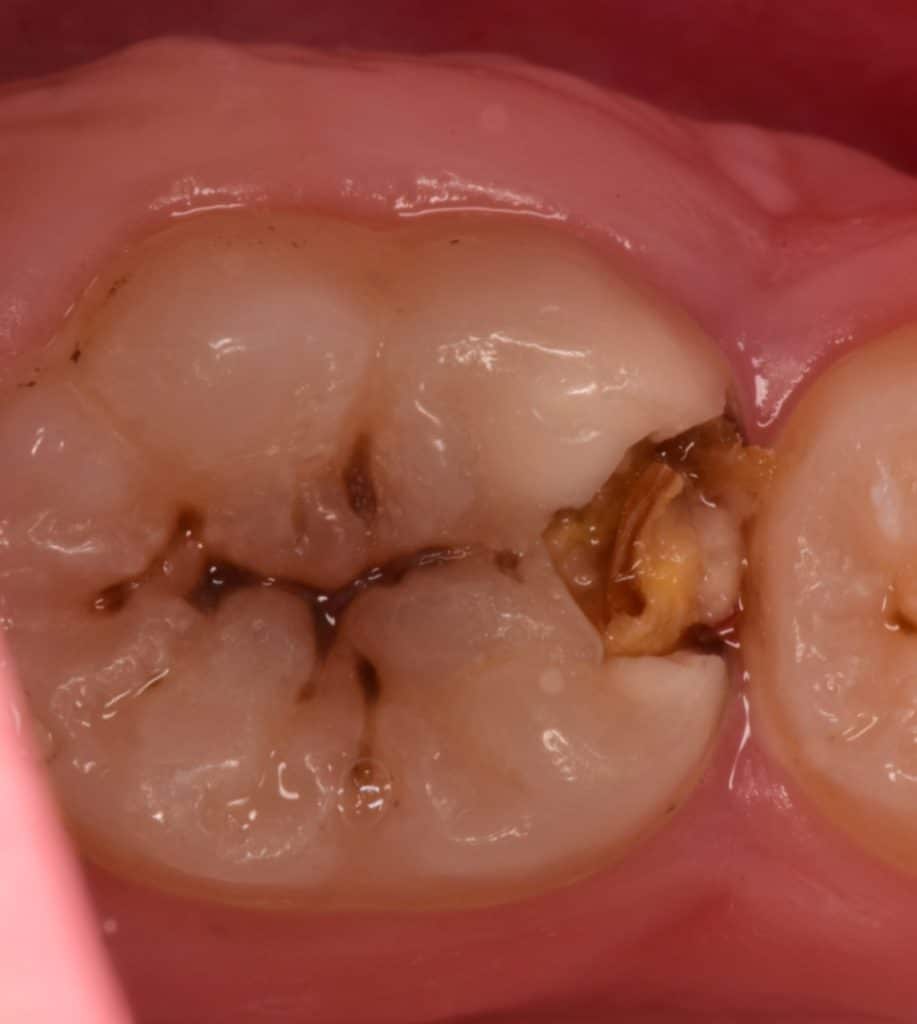

Initial situation

During cavity preparation, you can expect the depth of the cavity from this view

Multiple exposures due to the extension of the caries into the pulp